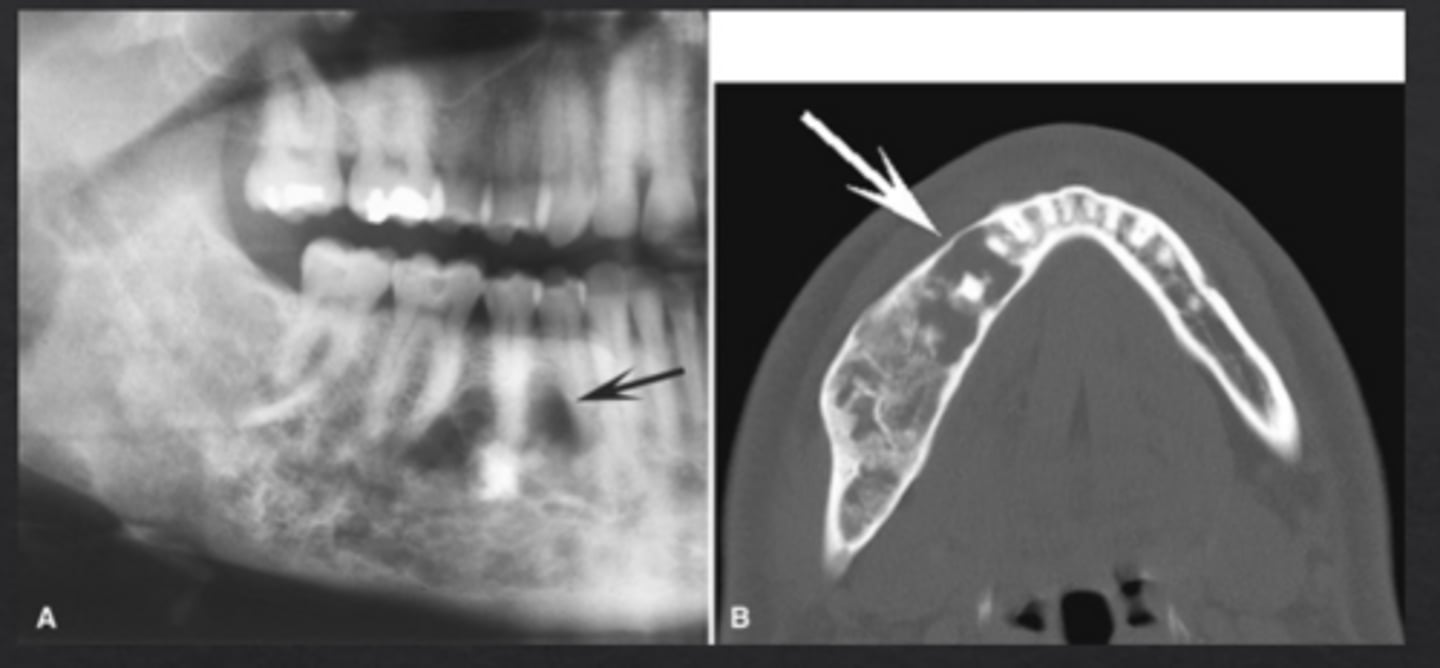

What is idiopathic osteosclerosis?

"Dense bone island" an area where normal trabecular bone is replaced with dense cortical bone

How does idiopathic osteosclerosis appear radiographically?

Region of dense radiopaque bone, blends with surrounding bone

Does idiopathic osteosclerosis typically affect adjacent structures?

No

What are exostoses or tori?

Outgrowths of cortical bone

How do tori appear radiographically?

Where are tori most commonly located?

Mid-palate (torus palatinus) and lingual mandible (mandibular tori)